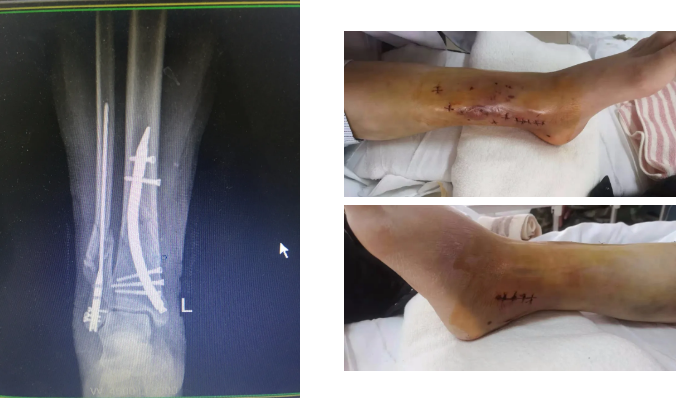

患者,女,54岁,因外伤后左踝部肿痛、活动受限3小时入院,入院后诊断为左胫腓骨远端骨折,入院后左侧小腿远端明显肿胀,畸形,压痛、叩痛明显,局部可见大量张力性水疱。骨一科王金台主任马上组织病例讨论,并制定详细周密的手术计划,同时在患者及家属知情同意后实施胫骨远端骨折逆行髓内钉内固定术+腓骨骨折髓内钉内固定术,手术顺利完成。手术切口小、创伤小,对骨折端的血运基本无破坏,术后拍片骨折复位固定良好。

手术后

胫腓骨骨折可采用钢板固定、顺行髓内钉固定等,对该患者而言,骨折线较低,顺行髓内钉存在远端把持力不足、可能影响膝关节活动等劣势。钢板固定为偏心型固定,力学稳定性远不如髓内钉的中心型固定。胫骨逆行髓内钉和腓骨髓内钉技术均为目前国内领先的新技术,在我省还鲜有应用。